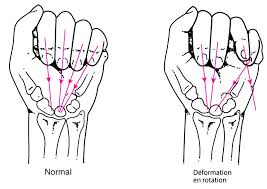

L’importance du déplacement, l’existence d’une rotation du doigt, l’âge, la latéralité du patient sont les éléments de choix de votre chirurgien.

Un trouble de rotation du doigt est également très gênant au quotidien.